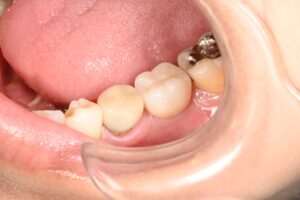

治癒待ち後の写真です。

インプラントに封鎖するためのカバーが付いている状態です、

この状態から型取りを行い仮歯を作っていきます。